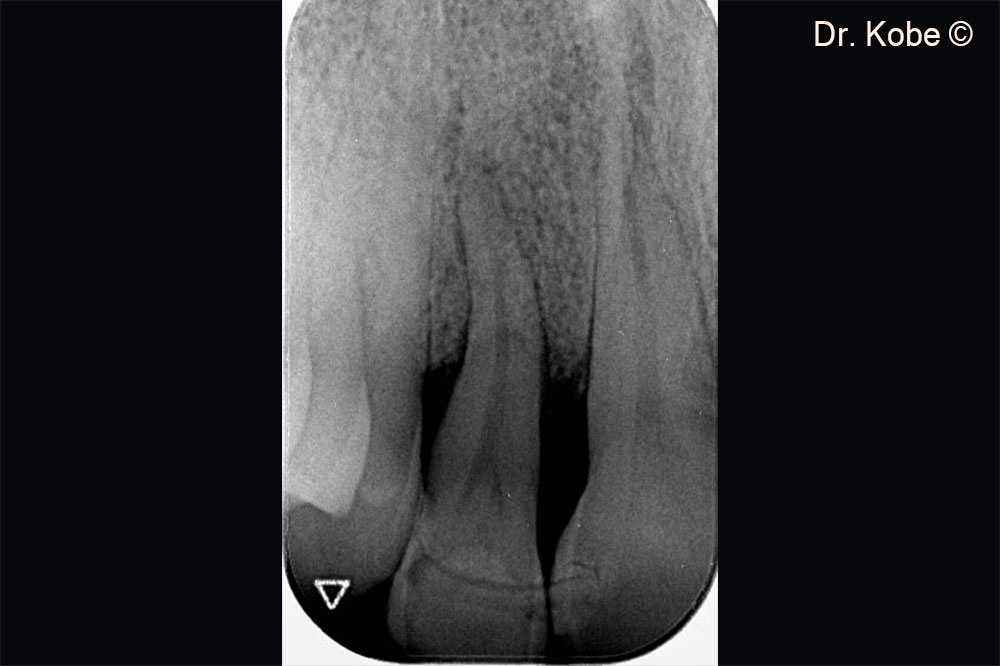

Vertical bone defect on the radiograph